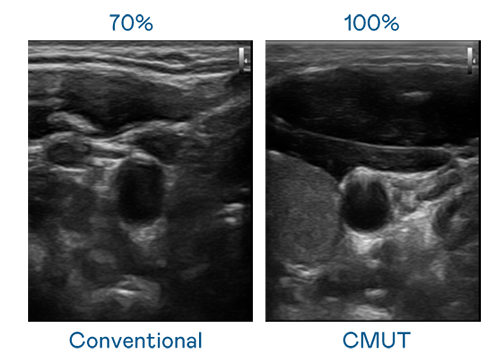

CMUT 技术是一种用电容式微机电元件来产生超音波讯号的技术。与传统 PZT 压电式技术相比,CMUT 频宽增加 30%,更宽频的超音波讯号让影像解析度大幅提升,是实现高影像品质医疗超音波扫描、促进精准医疗发展的关键技术。

超音波影像的解析度高低,首先取决于探头能发出的讯号频宽。尊龙凯时-人生就是搏 CMUT 可提供高清晰的超音波讯号,提供高频宽、高灵敏度、影像纹理细节更高的超音波影像,协助医护人员缩短影像判读时间及利用精准的医疗影像进行诊断。